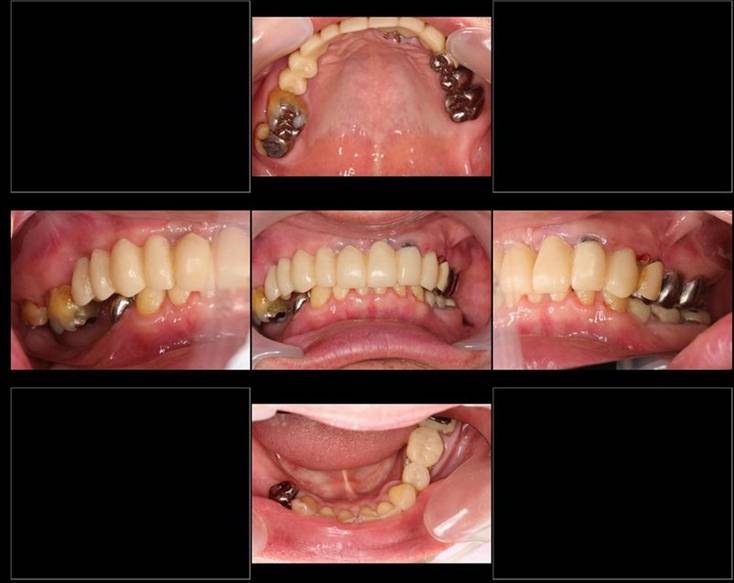

歯周病で抜歯せざるを得ず、インプラントを希望されたケース(使用インプラントはスプライン)

術前。すべての歯が歯周病の末期状態でブリッジ全体がうごいて噛めないとの訴え。右上の犬歯が腫れていました

固定式のブリッジが入っていましたが歯周病で動いています

下顎前歯部には歯石の沈着がみられます

術後。上部構造はハイブリッドレジンです。しっかり嚙めるようになり喜んでいただきました。

上顎

下顎

治療後。歯周病で失われた骨が回復しています。使用インプラントはスプラインツイストです。

上部構造装着後6年。ハイブリッドレジンを使用したため、少し艶がなくなってきました。上部構造の材料には金属、ハイブリッドレジン、セラミックなどがあります。セラミックはきれいですが欠けやすいため、最近はフルジルコニアを使っています。

上顎 少しすり減ってきました。

下顎。12か月に一度メインテナンスをしています。

インプラント装着後6年。順調に経過しています。12か月毎のメインテナンスをしています。